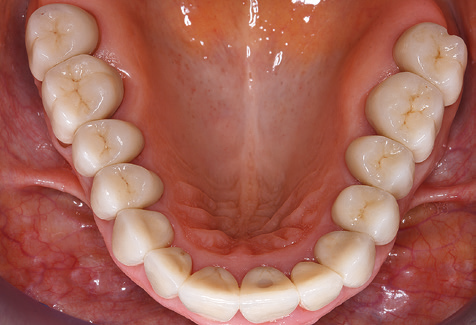

Good illumination of the working field facilitates the process considerably. The system used by the authors achieves this thanks to a 5x LED ring integrated in the handpiece. Naturally, a range of working tips for different indications is also offered. A straight, universally employable tip is the basic instrument required for machine cleaning of natural teeth (Fig. 5a and b). Curved tips, which allow access to exposed furcations, are also available for hard-to-reach areas in the posterior region (Fig. 6).

Fig. 4: Flexible probes with millimetre markings are recommended for the probing of dental implants (e.g. Colorvue Kit PCV11KIT6, Hu­Friedy). – Fig. 5a and b: A straight working tip (1P, W&H Dentalwerk Bürmoos GmbH) is a suitable instrument for use on all natural teeth. – Fig. 6: Curved working tips (3Pr/3Pl, W&H Dentalwerk Bürmoos GmbH) lend themselves to the processing of difficult-to-reach areas of the tooth and root surfaces (e.g. furcations). – Fig. 7: The tapered, hexagonal implant cleaning tip (1I, W&H Dentalwerk Bürmoos GmbH) permits atraumatic and efficient cleaning of the crown and abutment surfaces. – Fig. 8: Titanium and carbon curettes are suitable instruments for the manual cleaning of the implant surfaces.